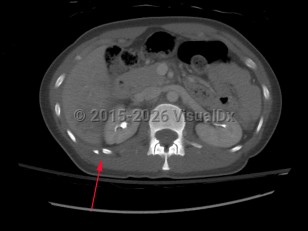

Fractures of the lower ribs (9-12) could indicate concomitant intraabdominal injury.